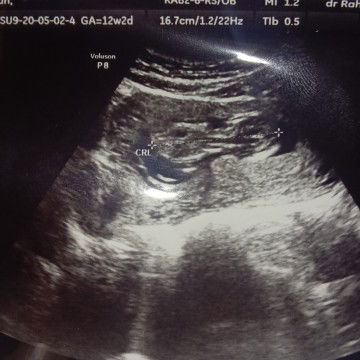

melanjutkan cerita yg kemarin agar tidak pd bingung #pejuanghisprung Part 1 : https://community.theasianparent.com/q/tadinya_saya_mau_simpan_cerita_ini_dalam_dalam_biarlah_kekal_dalam_ingatan_saya_/3918214?d=android&ct=q&share=true Setelah jesna didiagnosa kuning dan harus di nicu lg tp sy dan suami sepakat membawa pulang jesna kerumah. Alhamdulillah dirumah kami jesna tumbuh dengan pesat, dan tiap hari selalu di jemur dibawah sinar matahari pagi, juga tiap 2 jam sekali saya susukan. saat itu karena daya hisap jesna masih lemah sampai sy sendokkan 40ml/2jam sekali tanpa menggunakan dot, tp makin lama alhamdulillah jesna bisa beradaptasi dengan dot dan itupun harus saya trial beberapa bentuk dot dan botol nya. kesalahan saya disini adalah tentang minimnya informasi soal bingung punting sampai saya kira asi saya yg tidak enak membuat anak saya malas menyusu, tp dalam medis tidak ada asi yg tidak enak karena asi adalah makanan utama bayi yang baik daripada apapun. bulan pertama peningkatan berat badan jesna sangat signifikan sampai 1.4kg di usianya yang 40 hari tapii semua dimulai dari sini saat jesna lahir vaksinasi bcg sangat langka bahkan di daerah saya puskesmas dan BPM kosong, hanya ada di klinik dan rs itu pun mengikuti jadwal vaksinasi di tempat tersebut ahirnya jesna bisa vaksin saat 40 hari usianya, tp saat usia 2 bulan sy datang lagi untuk iimunisasi DPT 1 saat imunisasi ke 2 saya sempat bingung dan agak hawatir dengan BB jesna yg stuck di tempat sama seperti 20 hari sebelumnya saat vaksinasi BCG bidan bilang saat itu hal yg wajar, tp saya seorang ibu dan saya selalu baca soal tumbuh kembang anak, saya merasa jika ada yg tidak beres pada jesna. saya sempat menyalahkan asi saya yg sy fikir hanya banyak foremilknya sampai saya coba konsultasi online kapada konsultan lataksi ditambah sy harus jd momeping karena bingput jesna selang beberapa lama, tiba tiba jesna diare dan muntah bewarna kuning juga kondisi yg lemas, saat itu memang jesna sudah tidak mau menyusu. saya tau keadaan dimana anak saya tidur dan anak sy lemas, karena jesna adalah tipe anak yg sangat sangat aktif. tapi ini itu berbeda dari biasanya, katanya jika anak diare atau demam dibiarkan saja karena mungkin mau lebih pintar entah itu bisa tengkurap atau mengoceh. tp menurut saya tidak, anak sakit pasti ada indikasi tertentu ahirnya setelah suami sy pulang, sy masih ingat saat itu azan magrib saya dan suami buru buru ke IGD tempat jesna dulu dilahirkan disana saya bertemu dokter jaga, tanpa pemeriksaan cek lab darah dll, hanya ditanya keluhan apa, dan melihat jesna masih aktif lalu hanya diberikan oralit juga obat lambung untuk bayi dan saya disuru pulang saya tidak mau menyalahkan rs dan dokter umum yg merawat anak sy saat itu tapi yang pasti saat kembali kerumah jesna makin parah, sudah tidak mau menyusu bahkan perutnya kembung, nangis rewel pokoknya semalaman itu saya dan suami dibuat stress karena tangisan jesna sampai besoknya sy mau bawa jesna ke specialist anak untuk di cek lebih lengkap soal jesna tp saat subuh hari, hati saya sudah tidak enak, buru buru saya bangunkan suami saya minta antar ke IGD kemarin lagi karena posisi perut jesna sudah kembung dan muntah cairan bewarna kuning kenapa saya kekeh di rumah sakit sebelumnya? karena jesna lahir disana dan rekam medis jesna sudah tertulis disana sepanjang jalan saya cuman nangis saya takut kehilangan jesna anak pertama saya dan sampai disana sy bertemu dokter yg sama seperti malam sebelumnya dengan keluhan yg sama dan lebih parah ahirnya jesna di cek lab dan uuntuk kedua kali jesna harus diambil darah, andai kalian ada di posisi saya pasti teriris sekali hati seorang ibu melihat anaknya menangis harus merasakan sakit dan tak lama hasil lab keluar dengan hasil yg buat saya tersambar petir bagaimana tidak, dokter bilang HB jesna hanya 6.5 dan lekosit meningkat menjadi 40.000 YaAllah dosa apa yg saya lakukan dulu sampai anak saya menderita seperti ini, bayi usia 2 bulan harus mencari donor darah AB+ kl saya dan suami bisa mendonorkan darah kami akan kami donor, tp sayang saya bergolongan B dan suami A yg menyebabkan anak kami harus bergolongan darah langka masih ingat saat magrib tiba tiba jesna kejang, pertama kali dalam hidup saya melihat orang kejang dan itu anak saya sendiri saat itu juga suami saya mencari donor darah di kota lain tak lama setelah donor dan jesna di puasakan karena perut kembung anak umur 2 bulan itu harus puasa 4 hari tidak minum asi sama sekali, bibirnya sampai kering dan hanya nangis haus biarpun di inpus tp tetap saya rasa lapar tetap ada sampai dokter mendiagnosa jesna terkena hisprung deases untuk lebih jelasnya hisprung intinya bukanlah sebuah penyakit melainkan kelainan bawaan lahir Penyakit Hirschsprung adalah gangguan pada usus besar yang menyebabkan feses atau tinja terjebak di dalam usus. Penyakit bawaan lahir yang tergolong langka ini bisa mengakibatkan bayi tidak dapat buang air besar (BAB) sejak dilahirkan. Saraf di usus besar berfungsi untuk mengontrol pergerakan usus. Pada kondisi normal, pergerakan usus besar inilah yang mendorong feses keluar. Namun, pada penyakit Hirschsprung, saraf di usus besar tidak terbentuk dengan sempurna. Akibatnya, feses menumpuk di dalam usus besar. https://www.alodokter.com/penyakit-hirschsprung betapa hancurnya hati saya saat anak yg saya lahirkan di dagnosa memiliki kelainan lahir yg sangat bahaya sampai ahirnya dokter bedah umum rumah sakit itu menyerah tidak mau menangani karena beresiko tinggi terjadi kepada bayi jika kalian menjadi saya maka kalian pasti akan melakukan apa yg saya lakukan, melakukan yg terbaik untuk anak saya pun begitu, setelah saya pelajari ternyata jesna harus di rujuk ke rumah sakit yg lebih besar dengan dokter specialiat bedah anak untuk pertama kalinya saya naik ambulance dan saya harus membawa anak saya di ambulance tersebut tentunya dengan tatapan miris orang orang yg lewat yg melihat saya menggendong bayi saya yang masih menggunakan selang NGT dan inpusan kalopun saya bisa bicara saya mau bilang saya gamau dikasihani dengan tatapan kalian saya ga butuh belas kasih kalian seakan akan saya manusia paling menderita di dunia memang saya lagi terpuruk tp saat ini yg saya butuhkan hanya doa dan pemberian maaf dari orang orang yg mungkin saya sakiti.... part selanjutnya tentang cerita di rumah sakit rujukan... saya buat beberapa part ya soalnya kl di gabung akan panjang sekali sebelumnya saya ucapkan terimakasih untuk yg sudi membaca cerita saya